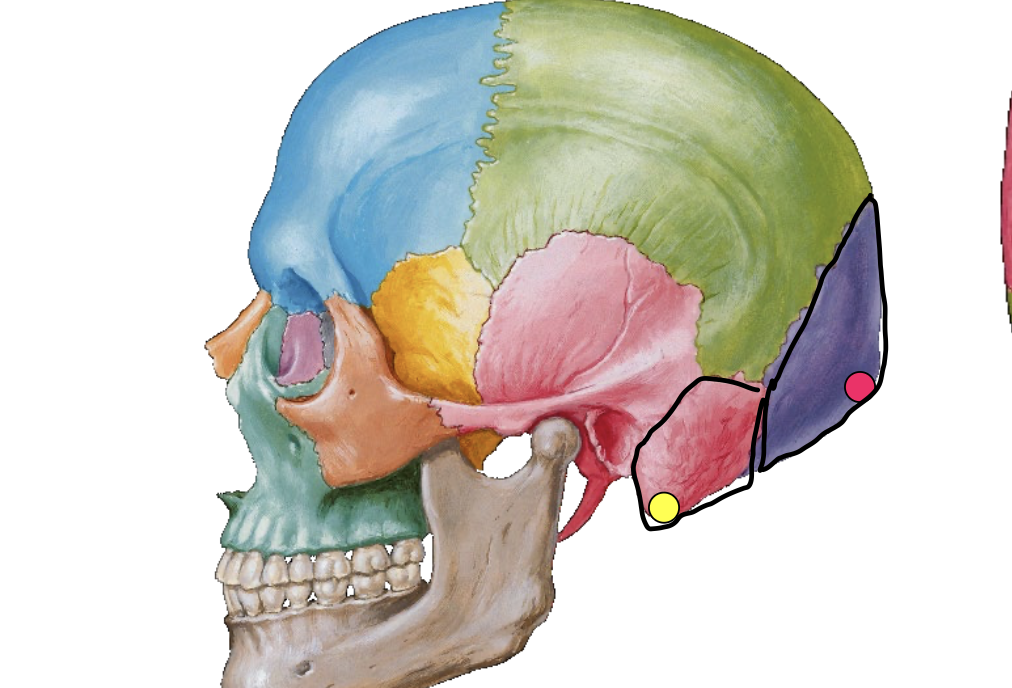

What is the pink dot locating in this image?

External occipital protuberance

What is the yellow dot locating in this image?

Mastoid process